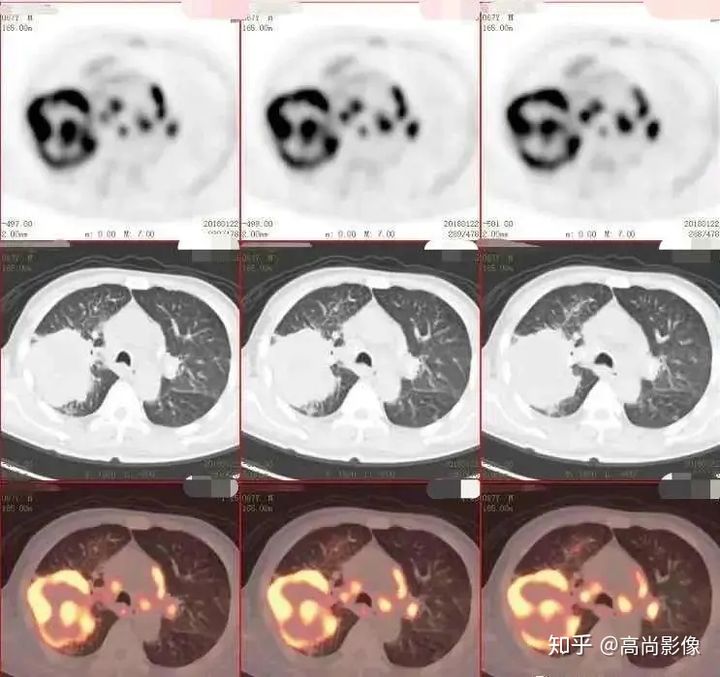

與方大爺有類似病情的一位患者,化療前后的PET/CT影像顯示,腫瘤得到了很好的控制。

肺癌化療前評估的MIP圖

(最大密度投影圖)

肺癌化療后評估的MIP圖

由此可見,惡性腫瘤化療前后的全身PET/CT評估有多重要,尤其對于惡性腫瘤患者來說,時間就是生命,早一天完善診斷,早一天得到正確的治療,預(yù)后就會更佳。